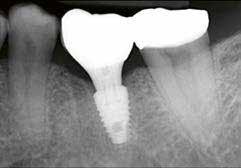

Hathetes gyógyulás után a lágyszövetek kiválóan gyógyultak, és minden implantátum megfelelően osszeointegrálódott, amelyet a radiológiai vizsgálat is megerősítetett (9. és 10. ábra).

A végső röntgenfelvételen láthatjuk az osszeointegrálódott implantátumokat, valamint a stabil kresztális gerincet az azonnal behelyezett, a rövid és a ferde, a tuberben elhorgonyzott implantátum körül (12. ábra).

A páciens teljesen elégedett volt az esztétikai és a funkcionális eredménnyel is, továbbá lenyűgözte a kezelés rövidsége, valamint a minimálisan invazív megoldása.